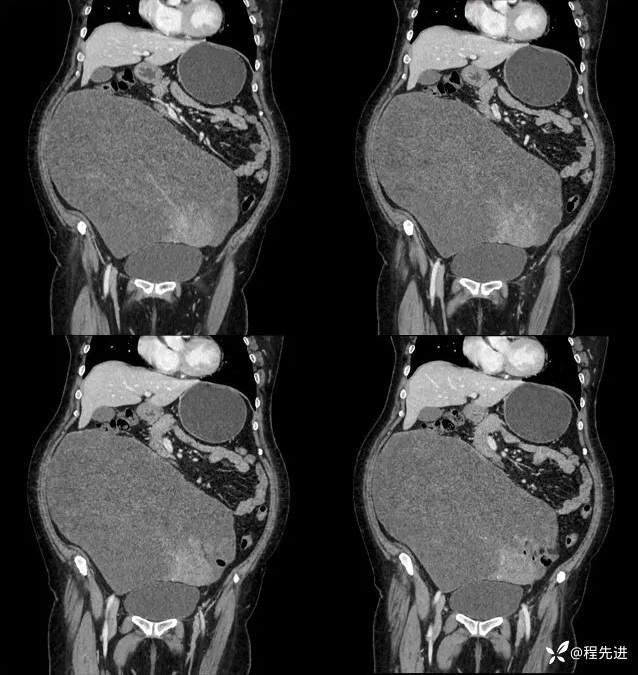

平扫:

动脉期:

门脉期:

延迟期: